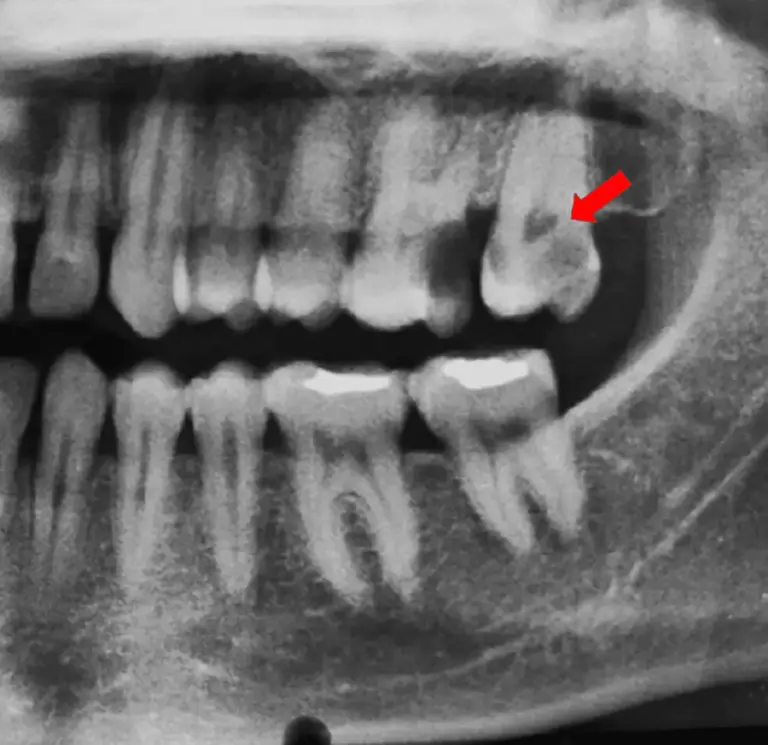

Phim X-quang toàn cảnh nha khoa

Đọc tiếpKhi quan sát phim x-quang toàn cảnh, bạn nên che đi phần ánh sáng bên ngoài xung quanh ảnh, làm…